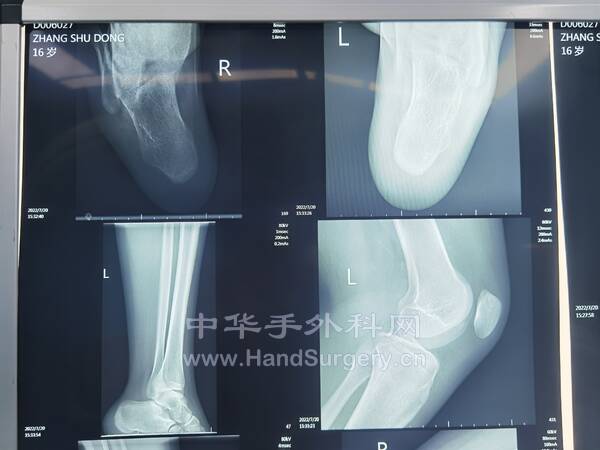

13岁女孩,双足拇外翻,老师建议手术治疗。

IMG_20220807_111810.jpg

IMG_20220807_144920.jpg

IMG_20220807_144949.jpg